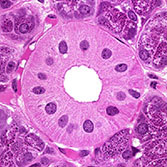

Histology is the study of the microanatomy of cells, tissues, and organs as seen through a microscope. It examines the correlation between structure and function.

Histology Guide teaches the visual art of recognizing the structure of cells and tissues and understanding how this is determined by their function. Rather than reproducing information found in a histology textbook, a user is shown how to apply this knowledge to interpret cells and tissues as viewed through a microscope.

Because of the high cost of purchasing (and maintaining) microscopes and preparing (or purchasing) slide collections, histology is often taught today without laboratories. A histology atlas is frequently used as a replacement. This is unfortunate because no matter how good the few images in a textbook or histology atlas are, they cannot replace the experience of viewing a specimen through a microscope.

Histology Guide solves this problem by recreating the look and feel of a microscope in an intuitive, browser-based interface.

An Aperio slide scanner was used to obtain a high-resolution image of each slide in its entirety. Large tissues are up to 34 GB for a single, uncompressed image of 150,000 x 75,000 pixels.

The contrast, color, and sharpness of each image were adjusted to at least maintain the appearance of the tissue as seen through a microscope. In many cases, these adjustments improved upon their visual appearance.

Unlike low-resolution images, users can interactively explore these large images by zooming-and-panning in real-time. A software-based virtual microscope (Zoomify HTML5 Enterprise) allows the examination of large and small structures in the same specimen.

This approach provides a more engaging learning experience and sense of scale, proportion and context that is not possible with a traditional histology textbook or atlas.

The Atlas of Human Histology: A Guide to Microscopic Structure of Cells, Tissues and Organs by Robert L. Sorenson and T. Clark Brelje provides a print version of the core slides from this website. Individual slides are presented as a series of images of increasing magnification to help convey a sense of scale and proportion. This atlas allows each student to have an easily accessible, printed summary of the essential slides from this website.